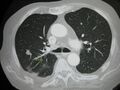

CT image of a lung metastasis

Metastatic cancer in the lungs